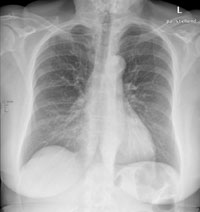

Eine 69-jährige Patientin klagt über einen seit mehr als 4 Wochen anhaltenden Husten mit wenig Auswurf. Die Frage nach Dyspnoe wird verneint. Fieber besteht keines.

Die körperliche Untersuchung ist unergiebig. Der behandelnde Arzt hat aufgrund der Raucheranamnese und des nicht enden wollenden Hustens ein Röntgenbild gemacht:

Thorax pa

Welche Befunde fallen auf (mehrere richtige Antworten möglich)?

Wie beurteilen Sie nun das Röntgenbild?